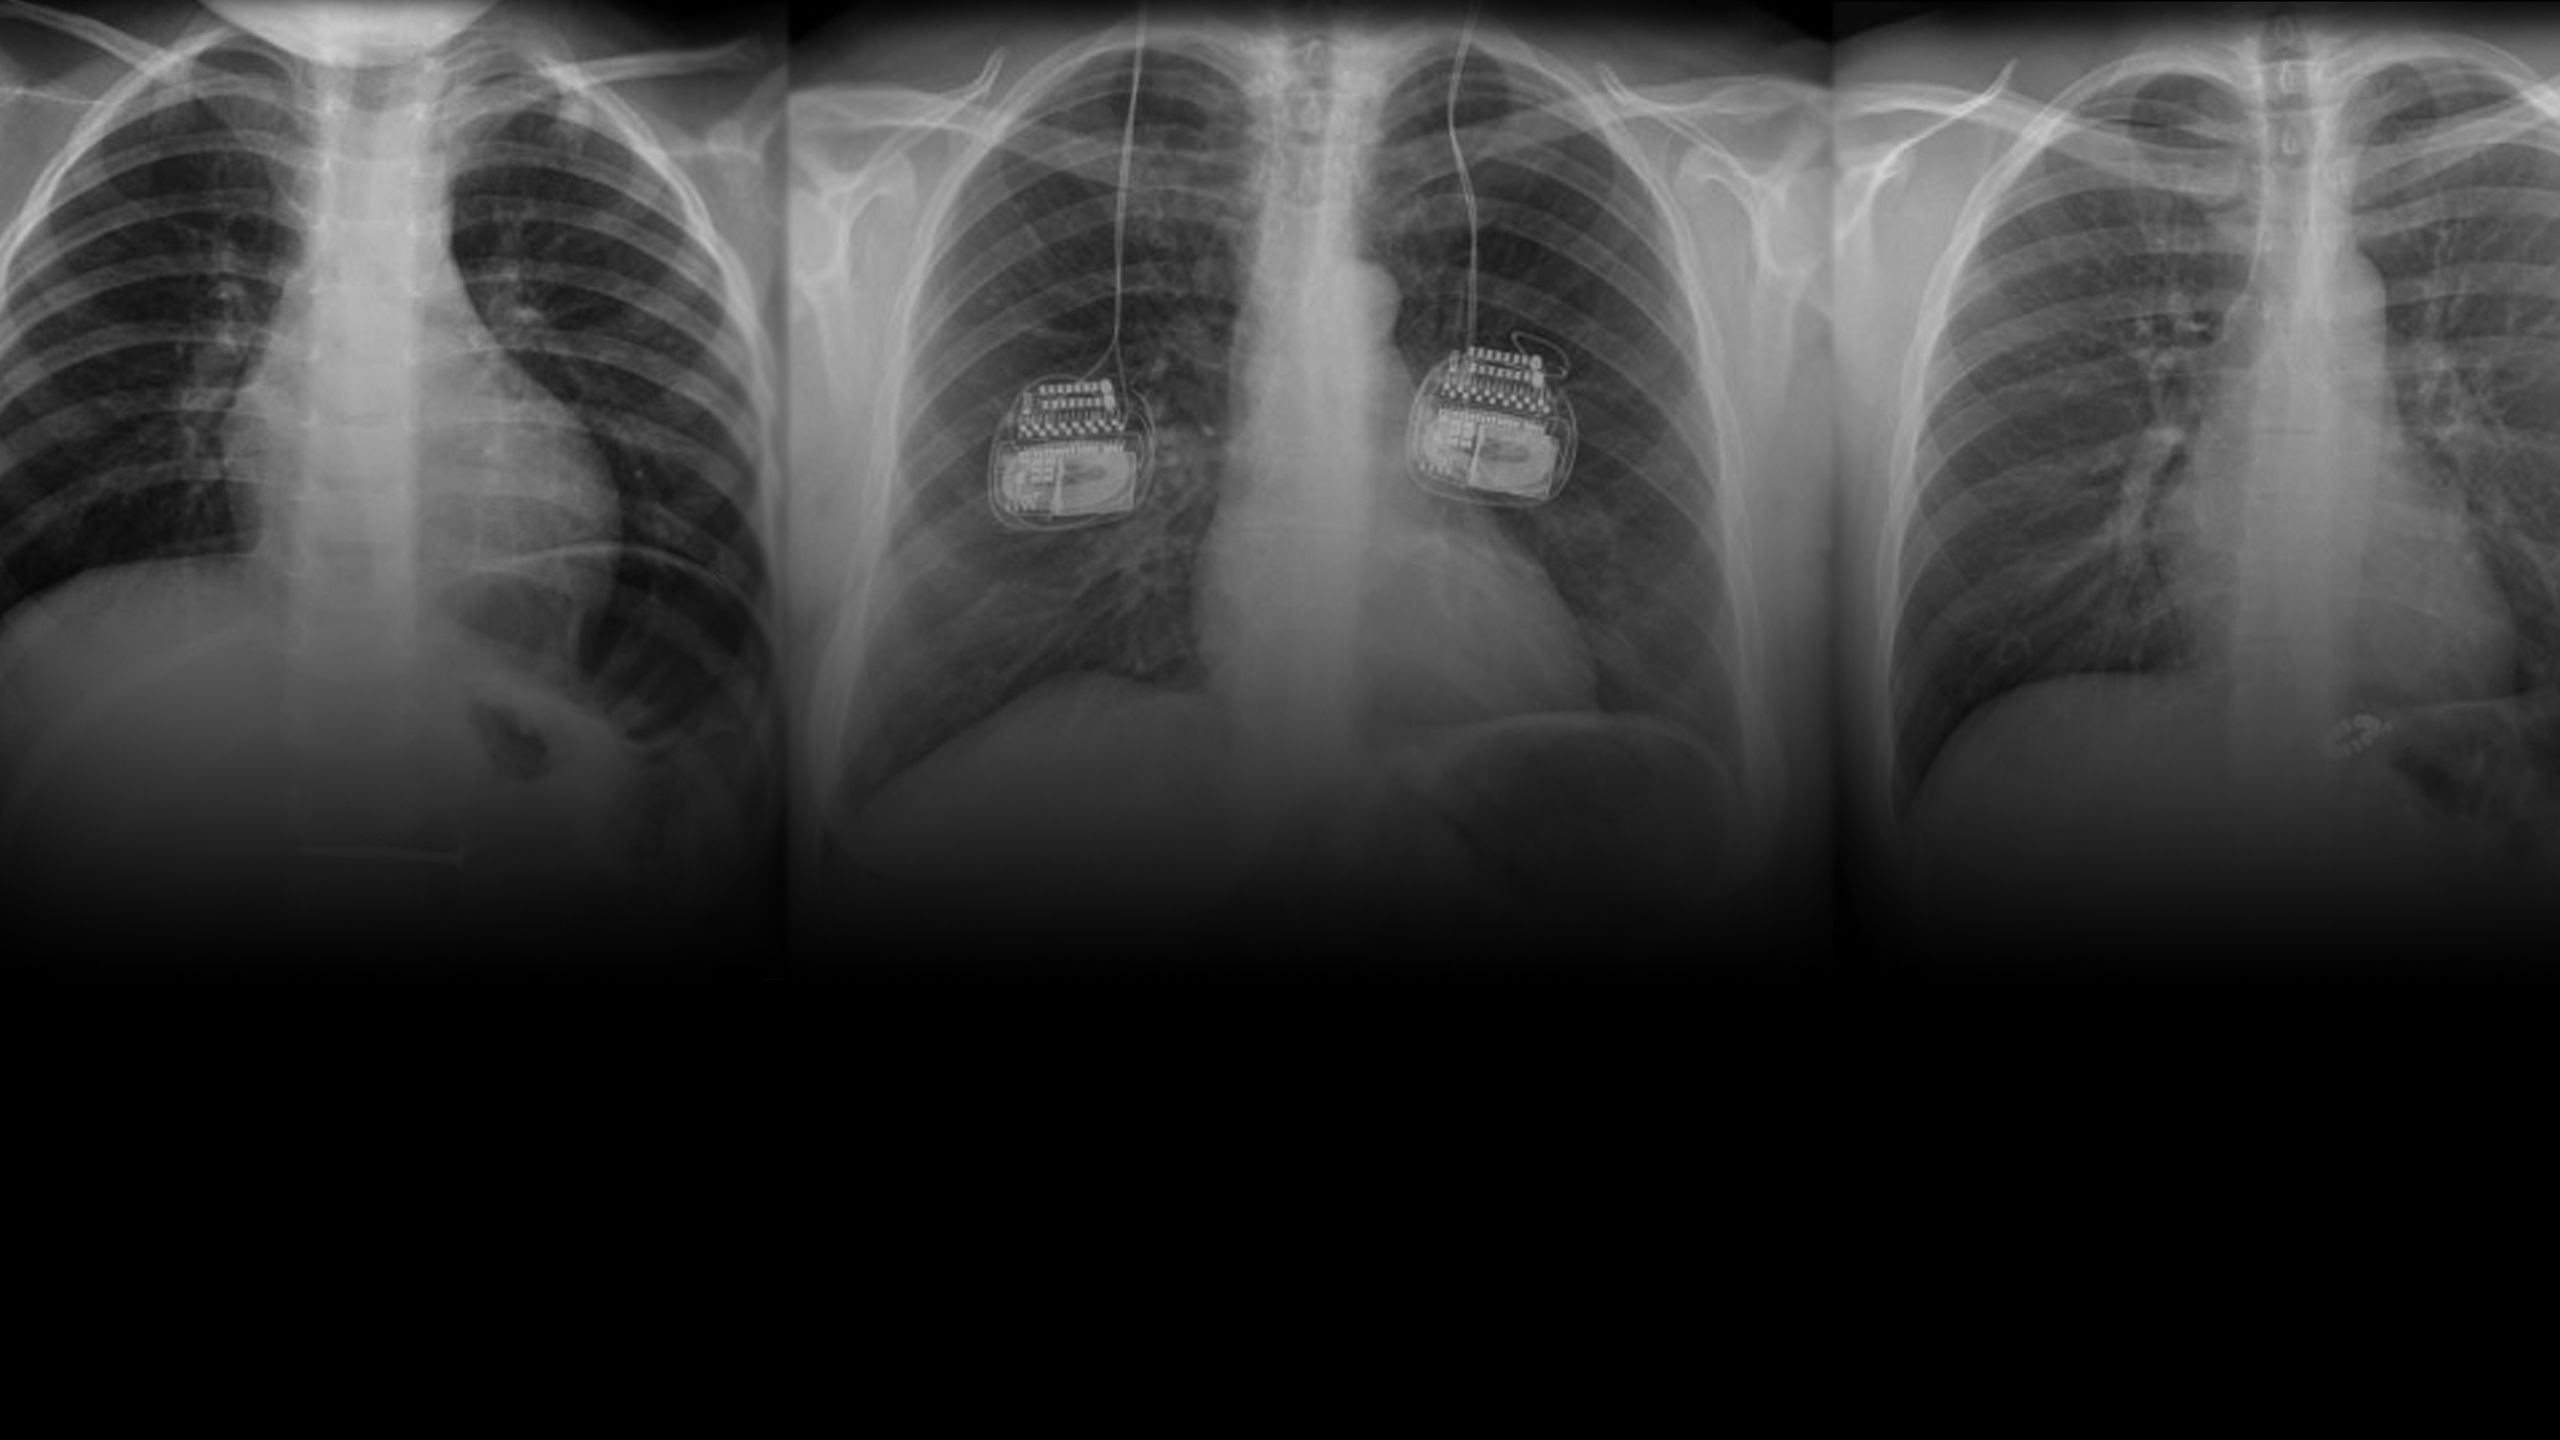

This e-learning programme is designed to raise awareness of different medical devices and to allow better utilisation of X-rays to confidently find and name them. While open to everyone, the training is specifically designed for Diagnostic and Therapeutic Radiographers for MRI safety screening. It is meant to highlight implants that may be specific to certain specialities; for example, cardiac or neuro, and therefore difficult to identify in departments outside of those specialities. Additionally, implants may be commonly known, but not easily recognisable on imaging. It also hopes to appeal to radiographers with different levels of experience and knowledge.

The training describes the appearance and most common locations of each implant and tries to explain various ways of differentiating between implants where possible. The reason for implantation is also stated to further assist identification and allow correlations to be made with the patient’s given information and medical records.

The ‘chest’ module represents the first of four to focus on implanted medical devices. The next modules in the series (abdomen/pelvis, head/neck and extremities) are under development and are due to be released soon.